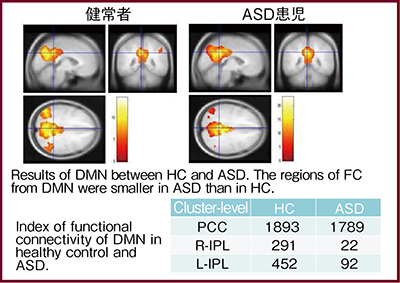

これまでのrsfMRIの研究から,代表的な安静時脳内ネットワークは7個あることが知られている。なかでも,default mode network(DMN)は安静時にネットワークの結合が強く,脳賦活時において結合が低下する部位とされ,多くの機能的疾患でDMNの異常が報告されている。自閉症(ASD)における自験例では,DMNが健常者と比較して低下しており,特に頭頂葉の低下が顕著であることが認められた(図6)。

rsfMRIはタスクを必要としない点で臨床応用しやすいが,rsfMRIで評価される神経ネットワークの生理的背景は不明瞭な点が多く,解析における再現性と定量性についての評価は今後の課題と考えられる。現状は,研究ツールから実用的プローブへの過渡期であり,今後の進展が期待される。

図6 自閉症(ASD)におけるrsfMRI自験例